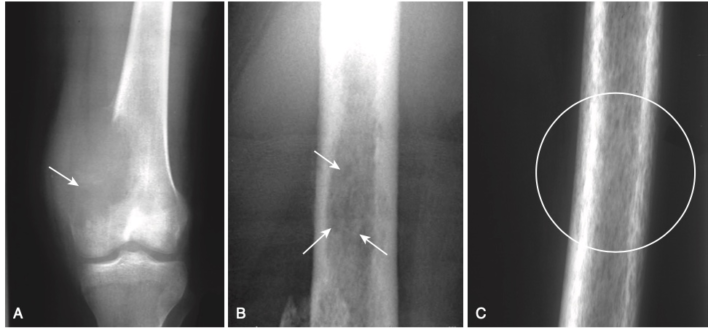

- Tiêu xương dưới màng xương, đặc biệt là ở mặt quay của đốt giữa của ngón trỏ và ngón giữa (Hình -2)

- Các tổn thương huỷ xương có biên rõ trong các xương dài, được gọi là các khối u Brown và hình ảnh dạng muối tiêu (salt-and-pepper) của xương sọ (Hình -4).

- (Các khối u Brown là những tổn thương lành tính biểu hiện sự tái hấp thu xương của một vùng khu trú của vỏ xương và thay thế bằng mô sợi và máu. Hàm lượng hemosiderin cao của chúng tạo một màu nâu đặc trưng vì thế có tên gọi là u Brown là màu nâu)